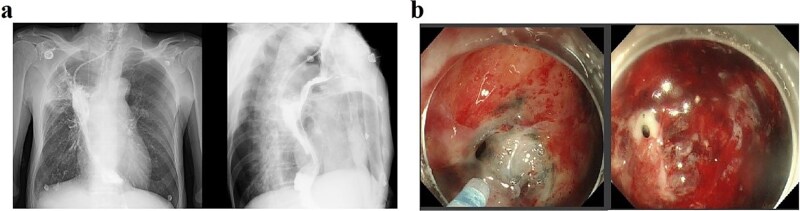

Esophagogastric anastomotic fistula is a common complication following esophageal cancer surgery, typically occurring within the first postoperative week. Conventional management requires prolonged fasting until complete fistula closure, which significantly impacts patient quality of life. We present a case of a male who developed an esophagogastric anastomotic fistula 2 months postoperatively, complicated by a concurrent gastrobronchial fistula. Endoscopic evaluation revealed persistent gastric wall defects at the fistula site. As the disease progressed, thickened visceral pleura formed dense adhesions with the damaged gastric tissue, effectively sealing the defect and preventing digestive fluid leakage into the thoracic cavity. By promptly promoting gastric emptying and reducing gastric acid secretion, the patient resumed oral intake without developing severe infections or complications.